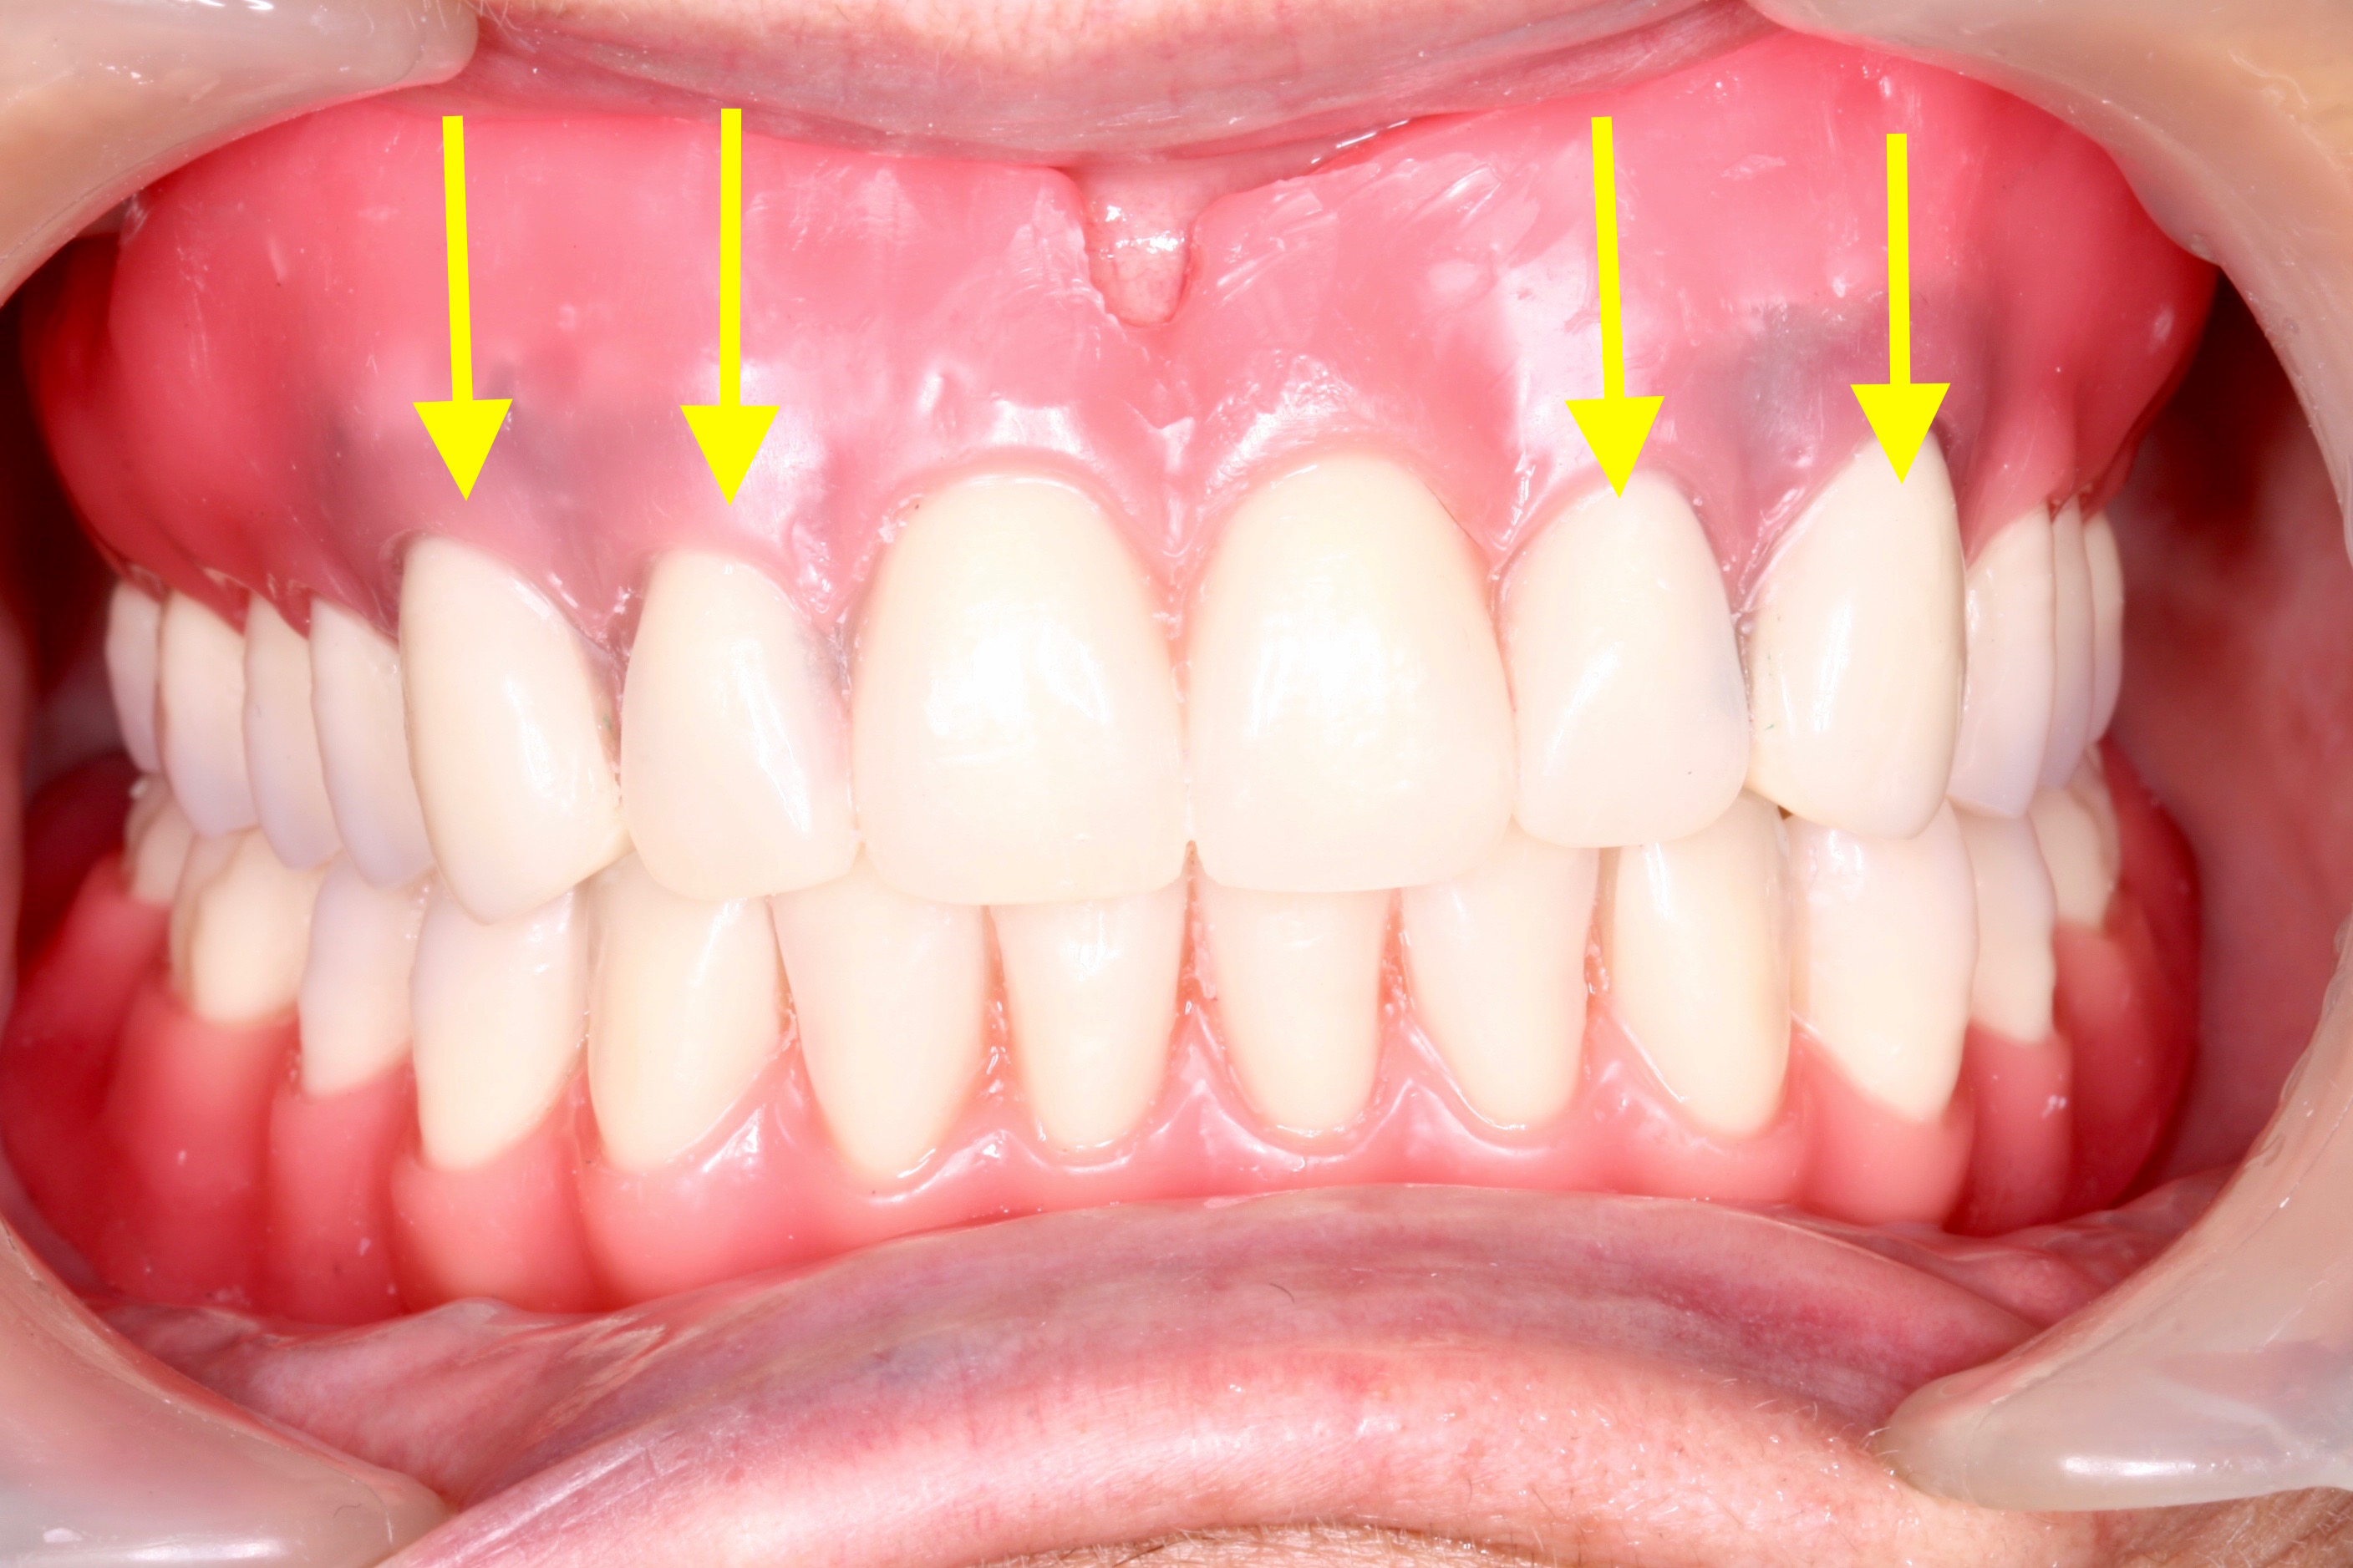

上がレジリエンツテレスコープ義歯、下が総入れ歯

![]()

総入れ歯の方

このような方のアゴは、アゴの骨が痩せて、総入れ歯が不安定になりがちです。

総入れ歯になったら、もう歯の治療が必要無いわけではなく、痩せてきたアゴの骨に合わせるように、修理したり新しく作るなどのメンテナンスが必要になります。

総入れ歯は、維持安定を求める歯が無いので、たくさんのノウハウやチェックポイントに注意を払って製作していく必要があります。